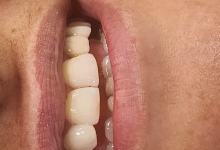

In acest timp are loc procesul de integrare in formatiunea osoasa. Succesul integrarii implantare este dat de catre formarea unei cantitati suficiente de celule osoase in jurul implantului dentar. In functie de necesitatile functionale sau estetice ale pacientului, urmeaza etapa protetica de realizare a lucrarilor de ceramica sau zirconiu. Implantul dentar este foarte important deoarece oasele maxilare se resorb, iar structura fetei incepe sa se modifice. In lipsa dintilor, atat masticatia cat si estetica au de suferit. O igiena necorespunzatoare, fumatul, bruxismul, etc., sunt factori de risc care duc la deteriorarea implantului. In perioada urmatoare dieta pacientului trebuie sa fie moale si la temperatura camerei.